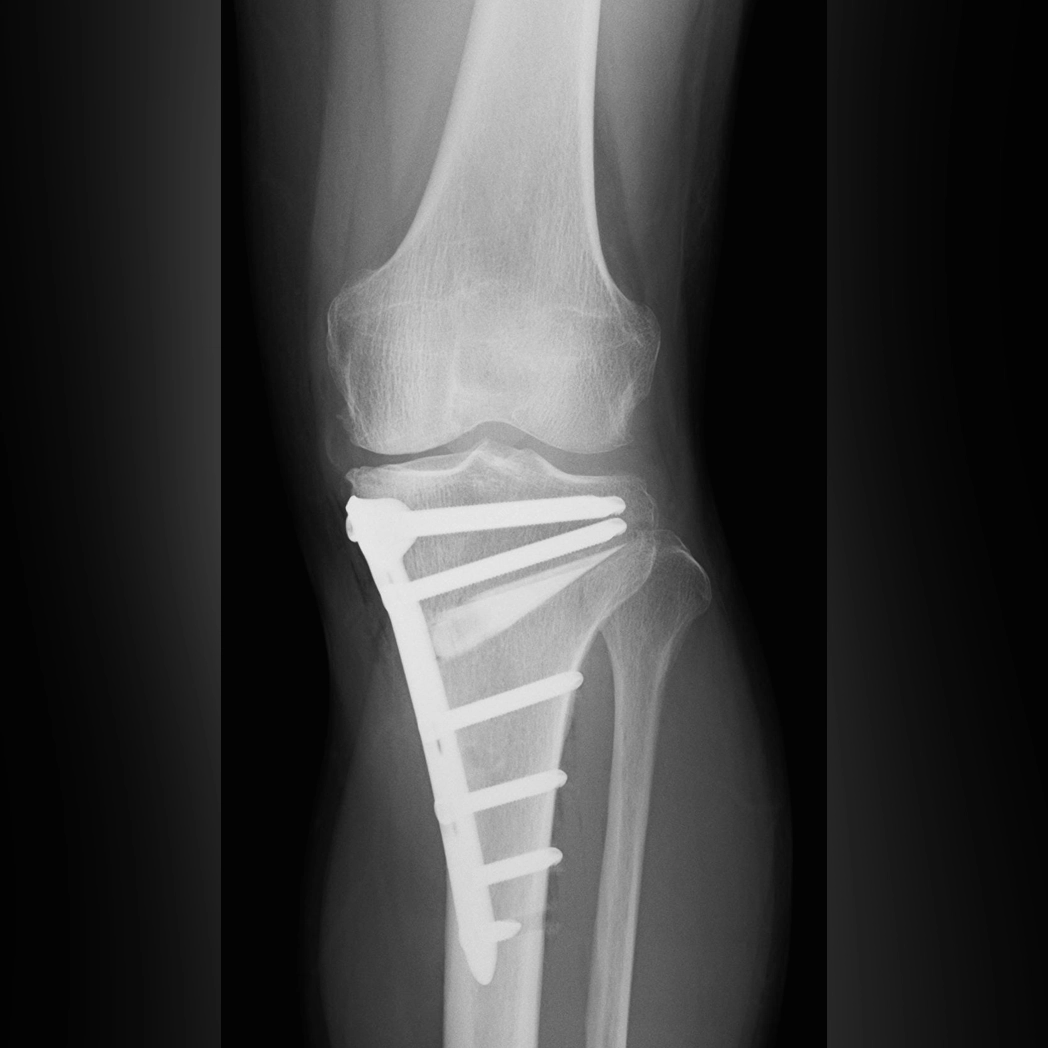

骨切り術

一方、日本で開発された手術法に骨切り術があります。これは、ひざの内側の軟骨がすり減ってO脚に変形した脚に対して、脛骨を切り、下腿を反対側に曲げて固定するというものです。私はこの骨切り術を対症療法だと考えてきました。なぜなら、O脚になった根本の原因(ひざ関節内側の軟骨減少)に手を加えず、正常な脛骨を切るからです。

では、骨切り術でひざの内側の痛みが軽くなるのはなぜでしょうか。それは、ひざの軸がまっすぐになることで、荷重の通り道がひざのより内側から関節の中央へと移動するためです。荷重がひざの中央を通るようになると、外側に残っていた関節軟骨が機能しはじめ、痛みなく歩けるようになります。実際、足を振って歩いているうちに、軟骨が失われた内側に線維軟骨が新たに形成されたという報告もあります。

つまり、骨切り術で痛みなく歩けるようになる仕組みは、“たつみ式保存療法”で痛みが軽くなる仕組みとまったく同じということです。わざわざ骨を切ってまで荷重軸をひざの中心に移動させずとも、歩き方を変えて「足放り体操」を取り入れることで線維軟骨をつくれば、同じ原理で痛みは治まり、O脚も改善していきます。